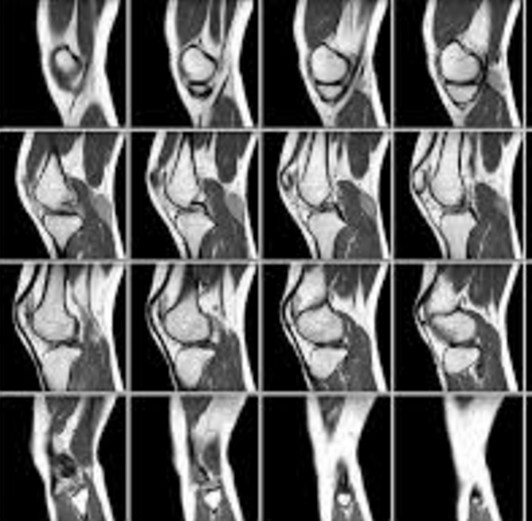

Фото МРТ суставов

Фото МРТ суставовДля того чтобы понять суть процедуры, можно посмотреть фото МРТ суставов. Во время обследования пациента сопровождает опытный медицинский персонал - специалисты помогают правильно расположиться на столе и контролируют состояние пациента. Изображения, получаемые во время сканирования, представляют собой серию послойных снимков с шагом от 1 мм и более.